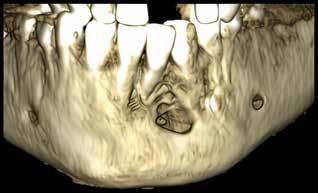

delta@delta-rengoering dk

deltaa@ddeltaa--rengoering d dk

www.delta-rengoering.dk

Hvis jobannoncen bliver indrykket på både Dentaljob.dk og i Tandlægebladet, får du 50 % rabat på annoncen i bladet

BAGGRUND – Centralt kæmpecellegranulom (Central giant cell granuloma – CGCG) er en sjælden, godartet læsion, som nærmest udelukkende er lokaliseret til kæberne. Det har kliniske, radiologiske eller histologiske ligheder med flere andre intraossøse læsioner. Ætiologien er stadig ukendt, men det viser sig, at genetiske mutationer er associeret med forekomsten af CGCG.

PATIENTTILFÆLDE – Tre drenge i alderen fem og seks år blev alle diagnosticeret med og behandlet for større CGCG-læsioner med få måneders mellemrum på Tand-, Mund- og Kæbekirurgisk Klinik, Aarhus Universitetshospital.

KONKLUSION – Det er yderst relevant at følge børn med spontant og tidligt tandtab i kommunal tandpleje. Ved mistanke om patologiske forandringer henvises til hurtig udredning og diagnostik i hospitalsregi for at klarlægge diagnose og minimere skader på blivende tandanlæg og omkringliggende strukturer.

EMNEORD Central giant cell granuloma | giant cell lesions | jaw neoplasm | benign bone diseases

CHRISTIAN LIND AXELGAARD, specialtandlæge i tand-, mund- og kæbekirurgi, Speciialklinik for kæbekirurgi, Silkeborg

KIMIE BOLS ØSTERGAARD, tandlæge i videreuddannelse til specialtandlæge i tand-, mund- og kæbekirurgi. Kæbekirurgisk Afdeling, Aalborg Universitetshospital

SVEN ERIK NØRHOLT, klinisk professor, specialtandlæge i tand-, mund- og kæbekirurgi, ph.d., overtandlæge, Afdeling for Tand-, Mund- og Kæbekirurgi, Aarhus Universitetshospital, og Sektion for Kæbekirurgi og Oral Medicin, Institut for Odontologi og Oral Sundhed, Aarhus Universitet

PER JOHAN SIXTEN BLOMLÖF, overtandlæge, docent, ph.d., specialtandlæge i tand-, mund- og kæbekirurgi, Afdeling for Tand-, Mund- og Kæbekirurgi, Aarhus Universitetshospital

STEEN BÆRENTZEN, overlæge, Patologiafdelingen, Aarhus Universitetshospital

OTTO THORSSON, specialtandlæge i tand-, mund- og kæbekirurgi, Afdeling for Tand-, Mund- og Kæbekirurgi, Aarhus Universitetshospital Accepteret til publikation den 13. maj 2025 Tandlægebladet 2025;129:928-34

CKorrespondanceansvarlig førsteforfatter: CHRISTIAN LIND AXELGAARD christianlindaxelgaard@gmail.com

ENTRALT KÆMPECELLEGRANULOM (CGCG) er en sjældent forekommende, benign, destruktiv læsion i kæberne, som af WHO karakteriseres ved en uindkapslet spredning af mononukleære spindelformede og polygonale celler med tilstedeværelsen af osteoklastlignende, multinukleære kæmpeceller i en vaskulær baggrund (1). CGCG udgør ca. 7 % af alle benigne, tumorøse læsioner i kæberne (2). CGCG ses med øget hyppighed ved patienter med RASopatier, som er fænotypisk homogene grupper af genetiske syndromer, forårsaget af patogenetiske stamcellevariationer i dele af RAS/mitogen-activated protein kinase (RAS/MAPK) pathway (Faktaboks) (3); heriblandt neurofibromatose type 1 (NF1) og Noonans syndrom (NS) (4). CGCG forekommer også sporadisk uden kendte stamcellemutationer. Ved patienter med sporadiske CGCG ses også ofte genmutationer i MAPK-pathway proteiner som KRAS, FGFR1 eller TRPV4, hvilket tyder på en genetisk årsag for udvikling af CGCG (5-8).

MAPK-pathway’en er en af de vigtigste og mest undersøgte signaleringspathways. Den er centrum i et molekylært signaleringsnetværk, der styrer vækst, proliferation, differentiering og apoptose. Meget forenklet signalerer den gennem tyrosinkinasereceptorer, der fosforylerer et målprotein som respons på en stimulus, og dette sætter gang i reaktioner, som afgrænses ved defosforylering af et protein downstream. Den fungerer således som en kontakt, der kan tænde og slukke. Hvis der er mutationer i et af proteinerne i denne pathway, kan denne sidde fast i tændt eller slukket tilstand (9).

Sporadiske tilfælde af CGCG forekommer oftest i den anteriore del af mandiblen og debuterer typisk i de første tre årtier af livet (5). I de syndromiske tilfælde ses mere end 90 % posteriort for hjørnetænderne (10).

Læsionerne vokser normalt langsomt, men aggressiv adfærd er ikke ualmindeligt (2). CGCG opdeles i nonaggressive og aggressive subtyper (11), hvilket er vigtigt for valget af behandling, da de aggressive subtyper har en højere recidivtendens (10,12). Histologisk er CGCG identisk med ”Brown tumor”, som ses ved hyperparatyroidisme, men denne tilstand rammer typisk patienter over 50 år. Derfor er det vigtigt med en

Fig. 1. Centralt kæmpecellegranulom i kæbe (A) med ossøs kæmpecelletumor/ osteoklastom i os sacrum til sammenligning (B). Kæmpeceller af osteoklastlignende type (tykke pile) ses af lille til moderat størrelse i kæmpecellegranulomet og af moderat til stor størrelse i kæmpecelletumorer. De mononukleære celler (tynde pile) ses tenformede i fibrøs matrix i kæmpecellegranulomet og anderledes plumpe uden matrixdannelse i kæmpecelletumoren.

Fig. 1. Central giant cell granuloma in the jaw (A) with giant cell tumor of bone/ osteoclastoma in the sacrum for comparison (B). Giant cells of osteoclast-like type (thick arrows) are seen in small to moderate size in the giant cell granuloma and in moderate to large size in the giant cell tumor. The mononuclear cells (thin arrows) appear spindle-shaped in a fibrous matrix in the giant cell granuloma and rather plump without matrix formation in the giant cell tumor.

endokrinologisk udredning for at sikre korrekt diagnose (13). Yderligere er det væsentligt at pointere, at CGCG ikke er det samme som den ossøse kæmpecelletumor/osteoklastom (Fig 1.), der praktisk taget aldrig ses i kæberne, men i stedet i lange rørknoglers epifyser og aksiale skelet og har en helt anden genetisk baggrund med mutation i H3F3A-genet, er endnu mere lokalt aggressiv og endda har en ganske lille risiko for hæmatogen metastasering og malign omdannelse (14).

PATIENTTILFÆLDE 1

Anamnese

En seksårig dreng blev henvist til en second opinion fra Pædiatrisk Afdeling, Aalborg Universitetshospital, hvortil patienten i første omgang var henvist med mistanke om malignitet eller kæmpecelletumor. Patienten havde spontant tandtab i fireårsalderen uden andre symptomer.

Klinik

Ved klinisk undersøgelse blev der observeret en blålig hævelse anteriort i underkæbefrontregionen.

Røntgen

CT-scanning viste diffus osteolyse i mandiblen fra midtlinjen og mod venstre, med involvering af -1,2. Destruktionen og ekspansionen havde ikke forårsaget resorption af tænderne (Fig. 2-3).

Histologi

Tidligere biopsi havde vist CGCG eller perifert kæmpecellegranulom. Ved ny patologisk gennemgang af præparatet blev CGCG bekræftet. Molekylærpatologisk analyse viste en KRASmutation, der understøttede diagnosen.

Patienttilfælde 1 – Præoperativ CT-scanning

Forløb